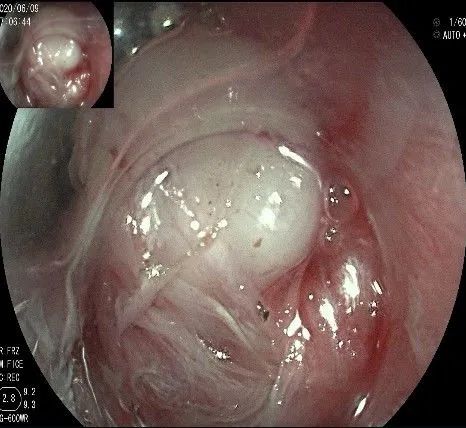

倒镜观察,可见贲门部一个明显的隆起,中央部分的凹陷,是4天前取活检留下的。

我们的思路:病变长径约2.0cm,位置活动,倒镜后先在胃底侧粘膜下注射,使病变向食管腔方向抬举,然后再在食管腔内做粘膜下注射切开,以获得一个好的术野,果然,注射后粘膜抬举明显,瘤体被挤向口侧。